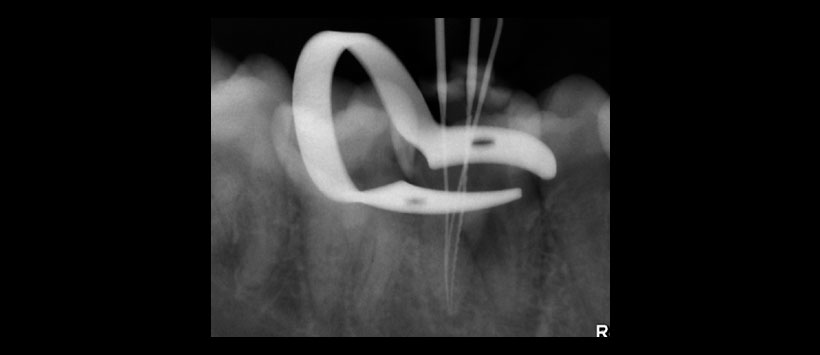

Figura 3. Longitud de trabajo en los conductos de la raiz distal